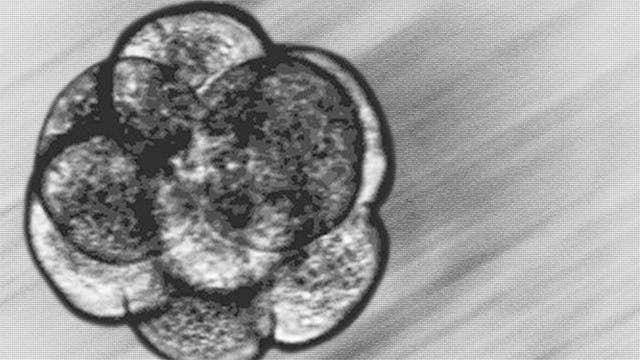

Claudia Cowan reports